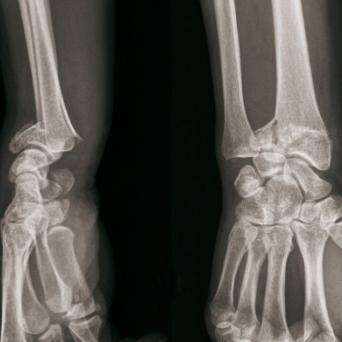

Microangiopathie thrombotique

La microangiopathie thrombotique (MAT) est une urgence médicale. Elle recouvre plusieurs pathologies aux mécanismes, tableaux cliniques et traitements distincts. Les progrès récents dans la compréhension de leur physiopathologie ont permis de mieux les identifier et les classifier, tandis que des thérapeutiques spécifiques en ont grandement amélioré le pronostic. Une identification précoce est donc cruciale.